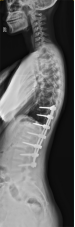

2.颈椎后路减压固定技术

颈椎后路减压技术适用于:脊髓型颈椎病伴发育性或多节段退变性椎管狭窄者;多节段OPLL;颈椎黄韧带肥厚或骨化所致脊髓腹背受压者。有节段性不稳定者可以同时行侧块钛板螺钉或经椎弓根螺钉内固定、植骨融合术。我科在区域内率先开展颈椎单开门、双开门技术,颈椎椎板切除减压椎弓根内固定术,均获得满意疗效。